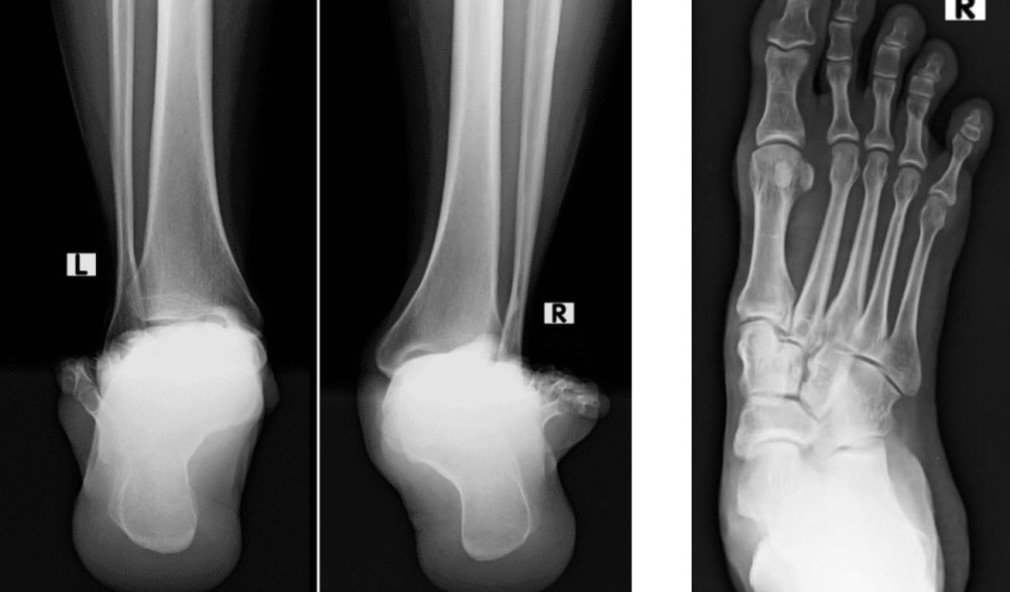

Röntgenbild juvenile Hallux valgus-Deformität

Fall des Monats – die juvenile Hallux valgus-Deformität

Die sportlich aktive 25-jährige Patientin litt an belastungsabhängigen Schmerzen unter dem linken Grosszehenballen. Sie berichtete uns, dass die Schmerzen schleichend kamen – zunächst tat der Fuss nur bei sportlichen Betätigungen wie z. B. beim Jogging weh, später dann auch bei normalen Alltagsbelastungen.